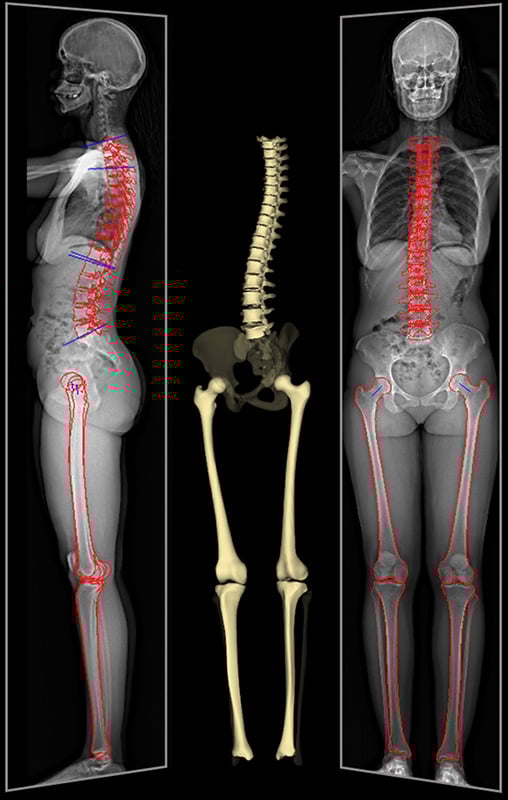

EOS can also support orthopedic surgeons with their presurgical planning, because it records and displays the patient’s anatomical structures in their true, size and volume, lengths and angles. This allows surgeons to perform highly precise presurgical planning and postsurgical assessment for hip replacement and knee replacement surgeries.

EOS preoperative imaging of a patient with 3D renderings and measurement of a hip replacement implant.

EOS full-body imaging of a patient showing 2D X-ray images and 3D rendering of the spine, hips and leg bones.

In some cases, an EOS scan can be used instead of a CT scan. For example, precision measurements of a patient’s leg length can be measured from an EOS scan in place of a CT scanogram, which is traditionally used to measure limb length discrepancy.